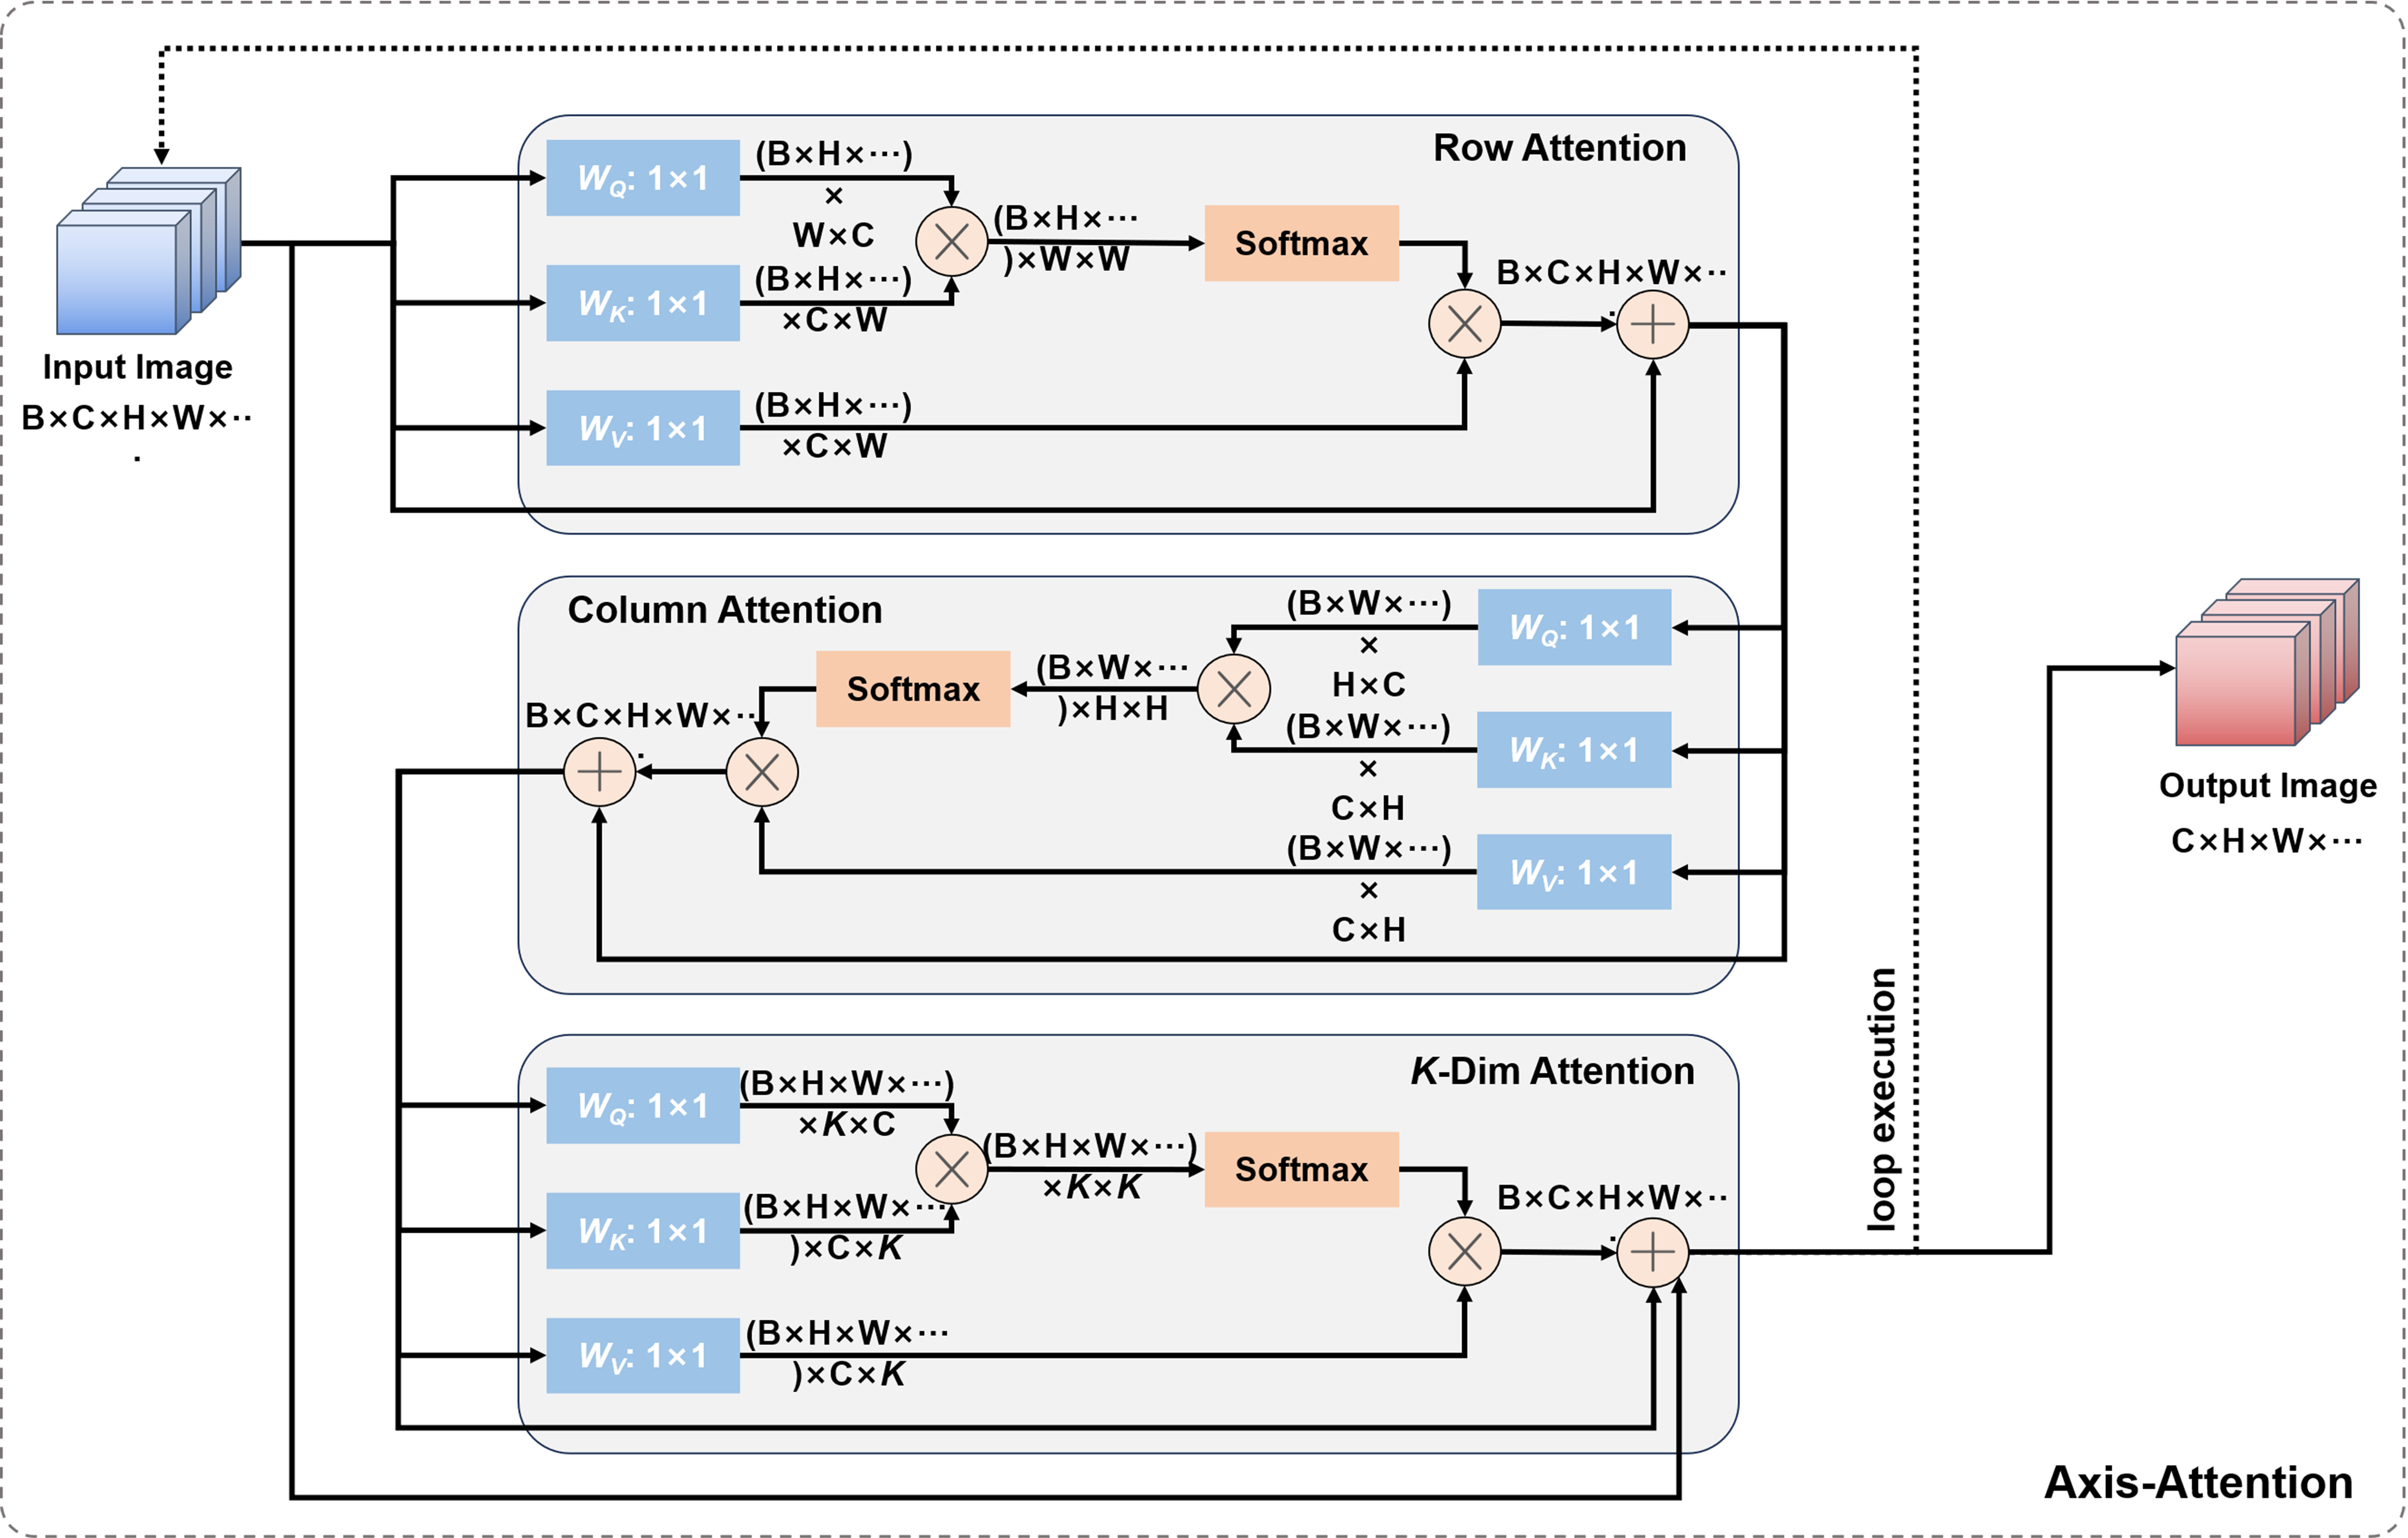

In addition, we also introduced axial attention mechanism to the bottleneck layer of the network, which was proposed by Ho et al.[21] [Figure 6]. Axial attention is used to extract relevant information between different parts of the image, and is applied in low-resolution images to reduce computational complexity.